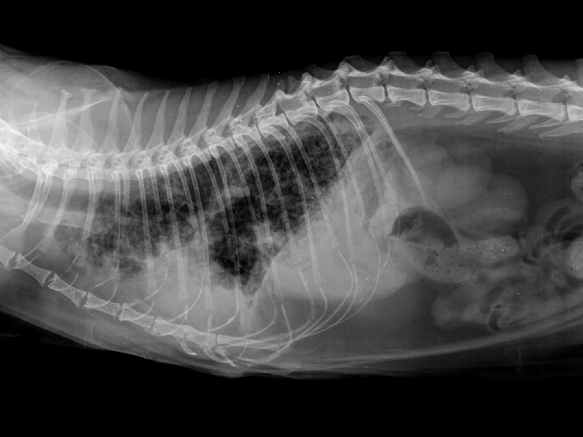

Mercredi 6 Janvier 2021 Animaux de compagnieRadiographie d'un profil métastatique d'un carcinome mammaire félin montrant des métastases de type miliaire (classique dans cette espèce) ainsi qu'un épanchement pleural (facteur de mauvais pronostic pour cette étude).

© Didier Lanore